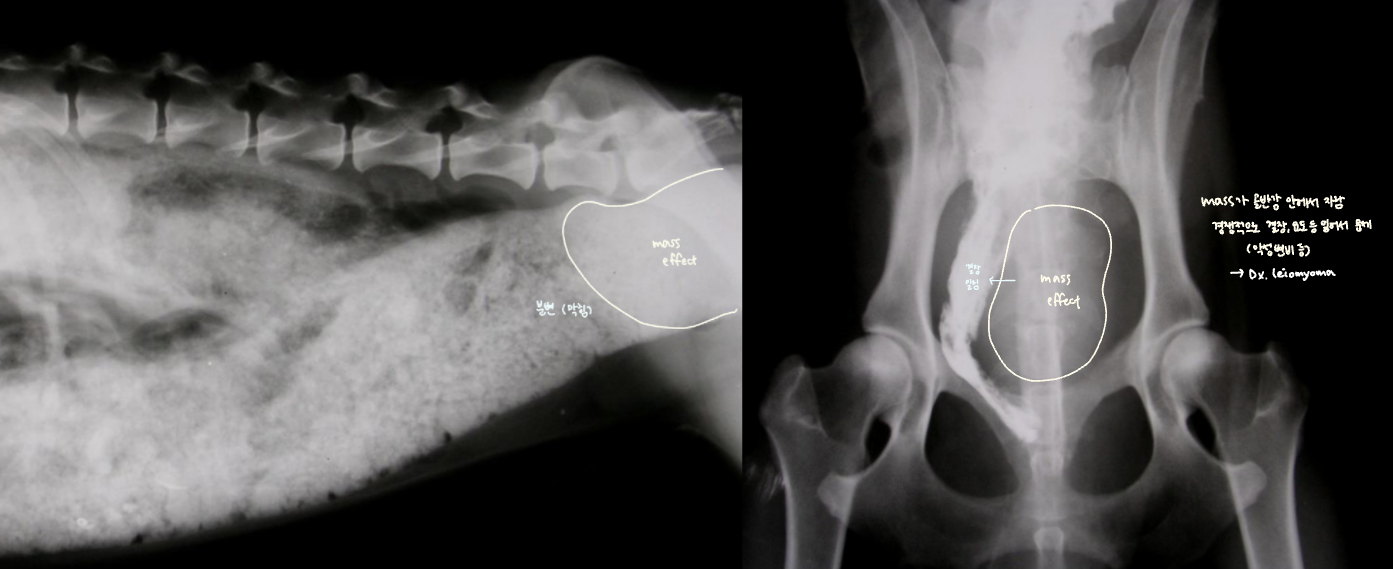

โ ๊ณจ๋ฐ๊ฐ ๋ด์์ ์๋ mass

- 4๊ฐ์์งธ ์ฌํ ๋ณ๋น + ์์๋ถ์ง, ์ฒด์ค ๊ฐ์, ๊ฐํ์ ๊ตฌํ ๋ก ๋ด์.

- Mass๊ฐ ๊ณจ๋ฐ๊ฐ ์์์ ์๋ผ๋ฉด ๊ฒฐ์ฅ๊ณผ ์๋๋ฅผ ๋ฐ์ด๋ด๊ณ , ์ ์ฑ ๋ณ๋น๋ฅผ ์ ๋ฐํจ.

- Leiomyoma๋ก ์ง๋จ๋จ.

โ ๋ด๊ฐ ์์ชฝ์์ ์๋ mass

- ๊ณจ๋ฐ๊ฐ๊ณผ ๋ฌ๋ฆฌ ๋ณต๊ฐ์๋ ์ฌ์ ๊ณต๊ฐ์ด ์์ด, ๋ด๊ฐ ๋ฐ๊นฅ์์ ์๊ธด mass๋ผ๋ฉด ๊ธธ์ ๋ง์ง ์์.

- ๊ทธ๋ฌ๋ ๋ด๊ฐ ์์ ์๊ธด mass๋ผ๋ฉด ๋ถ๋ณ์ด ๊ณ์ ์ถ์ ๋จ.

- ์กฐ์์ ๋ ์ผ์ ํ ๋๋น๋ก ํต๊ณผํ์ง ๋ชปํ๊ณ ๋งํ.